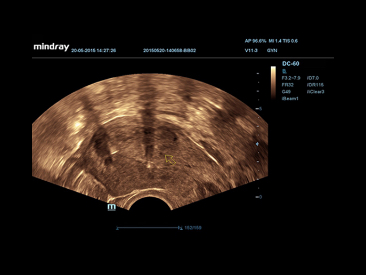

PSH??(Phase Shift Harmonic Imaging)

Purified Harmonic Imaging for better contrast resolution providing clearer images with excellent resolution and less noise.

iBeam?

Permits use of multiple scanned angles to form a single image, resulting in enhanced contrast resolution and improved visualization.

iClear?

Gain improved image quality based on auto structure detection

?┬Ę Sharper & Continuous Edges

?┬Ę Smooth Uniform Tissues

?┬Ę Cleaner ŌĆśno echo areasŌĆÖ